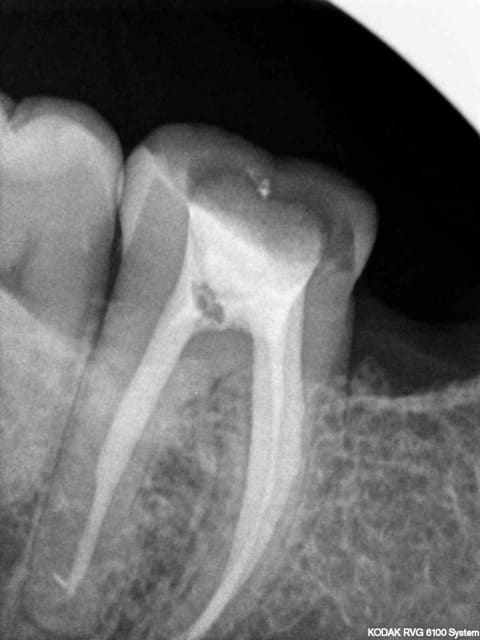

Ne leur dis surtout pas que tu as fait une faute. A la radio, ton obt est bonne.C'est tout.

Ton endo était pas mal.

C'est étonnant que le matériau d'obturation qui était dense en 2011 se soit dégradé à ce point et si vite.

Il est possible qu'il y ait autre chose (perfo latérale un peu en dessous du plancher, fracture de la racine MV).

Pour moi jusqu'à preuve du contraire c'est un alea.

Tu veux dire que, sur la radio, c'est à peu près blanc jusqu'au bout de la racine?

Parce que c'est tout ce qu'on peut dire sur cette endo. :-)))

Par contre à ta place je ne contesterais rien du tout, t'es en tort à 300%. J'espère pour toi que toutes tes endos ne sont pas comme ça. Certains me diront que je suis sévère blablabla "ça t'es jamais arrivé de rater" etc, mais en sortant de la fac faire ça je trouve ça honteux.

Mets au moins un cône un minimum calibré. La gutta ne "disparaît" pas.

Completement d'accord avec enlaye pour le multifactoriel ;l'infection est inter radiculaire , suite a une recession parodontale importante ,il suffit de voir la radio. Le retraitement (avec ou sans digue, :-)) est bien, mais ne donnera rien de plus!

Pour l'endo, c'est vrai que la disparition du matériaux d'obturation ne plaide pas en la faveur de notre jeune confrère.

La radio post-op du 15/11/2011 semble montrer la présence de cône de gutta dépassant coronairement . L'erreur ne viendrait-elle pas d'une empreinte de l'ic dans la foulée .

la préparation a retiré les cônes laissant le ciment endodontique.

Concernant une lésion interradiculaire je suis dubitatif en voyant uniquement cette radio .